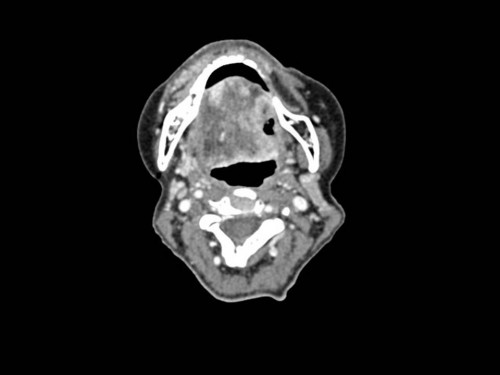

Makroskopie - intraoral präoperativ